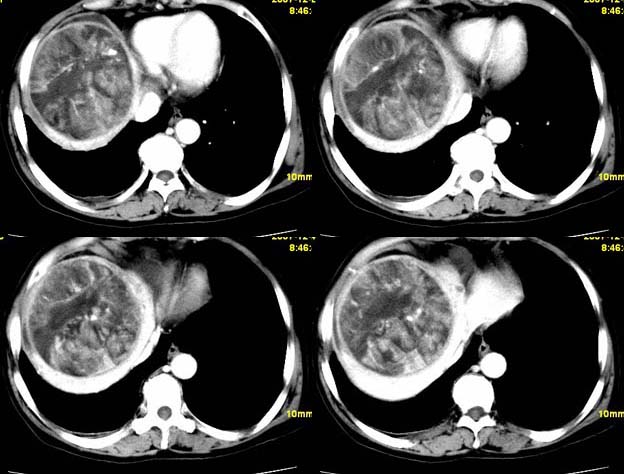

增强

支持;肝aml-------脂肪成分,中心血管征,延时强化.